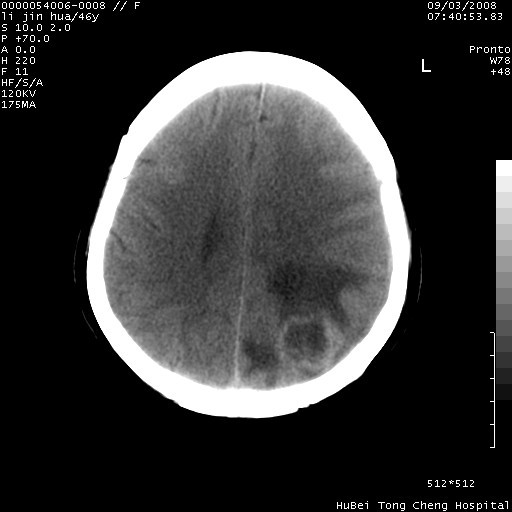

以下是引用panyishengct在2008-9-6 1:47:00的发言:[br]病史?[br]左侧枕/顶叶见一等/低混杂密度占位,壁完整,厚薄较均匀,其前方似有一类似小病灶,周围有水肿带,请结合病史考虑,脓肿可能,不排外转移瘤或胶质瘤,建议增强扫描。